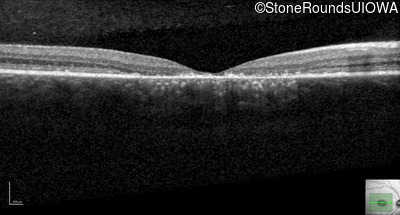

Optical Coherence Tomography - Right - 20/125 sc

Exemplar / OCT Stack

OCT Stack